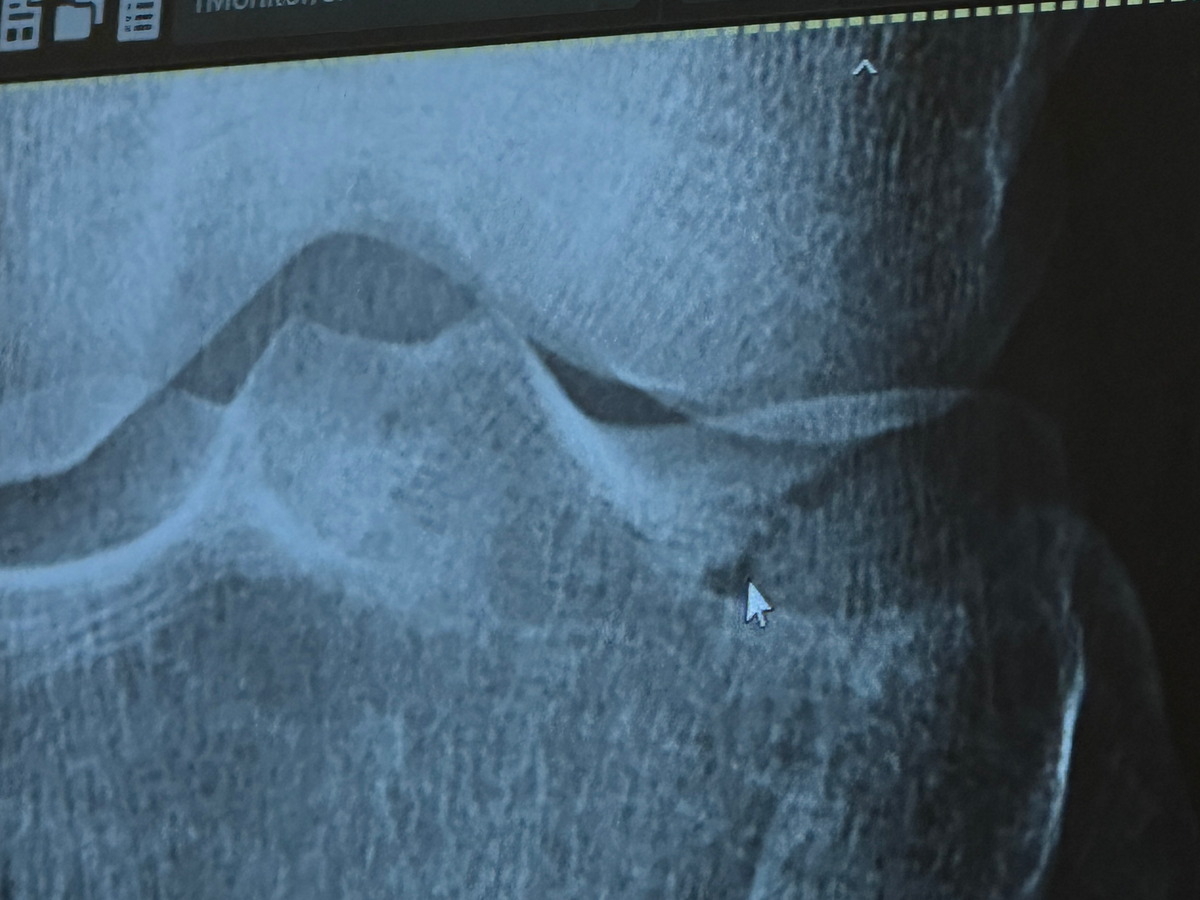

On July 28th, 2025, our beloved friend Xochi was seriously injured during Muay Thai training. She suffered a tibial plateau fracture and a torn MCL — painful injuries that require extensive recovery.